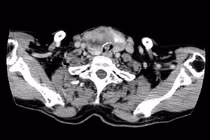

Bệnh viện Bãi Cháy (Quảng Ninh) đã phẫu thuật thành công cho trẻ 12 tuổi mắc ung thư tuyến giáp di căn hạch cổ. Đây là trường hợp bệnh nhân ung thư tuyến giáp trẻ tuổi nhất từng được phẫu thuật điều trị tại bệnh viện.